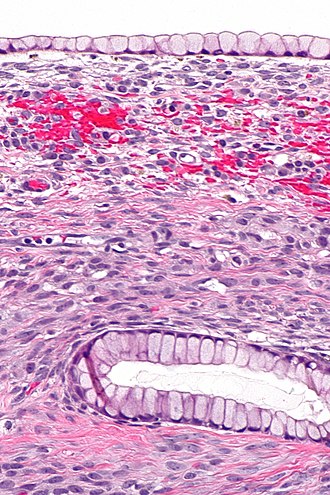

Ovarian mucinous cystadenoma. H&E stain. | |

Microscopic

Features:

- Cysts lined by a simple mucinous epithelium.

- No cytologic atypia.

Note:

- A borderline component may be present but must be <10% of the tumour.[4]

- Lesions with <10% borderline component are known as mucinous cystadenoma of the ovary with focal proliferation or mucinous cystadenoma of the ovary with focal atypia.